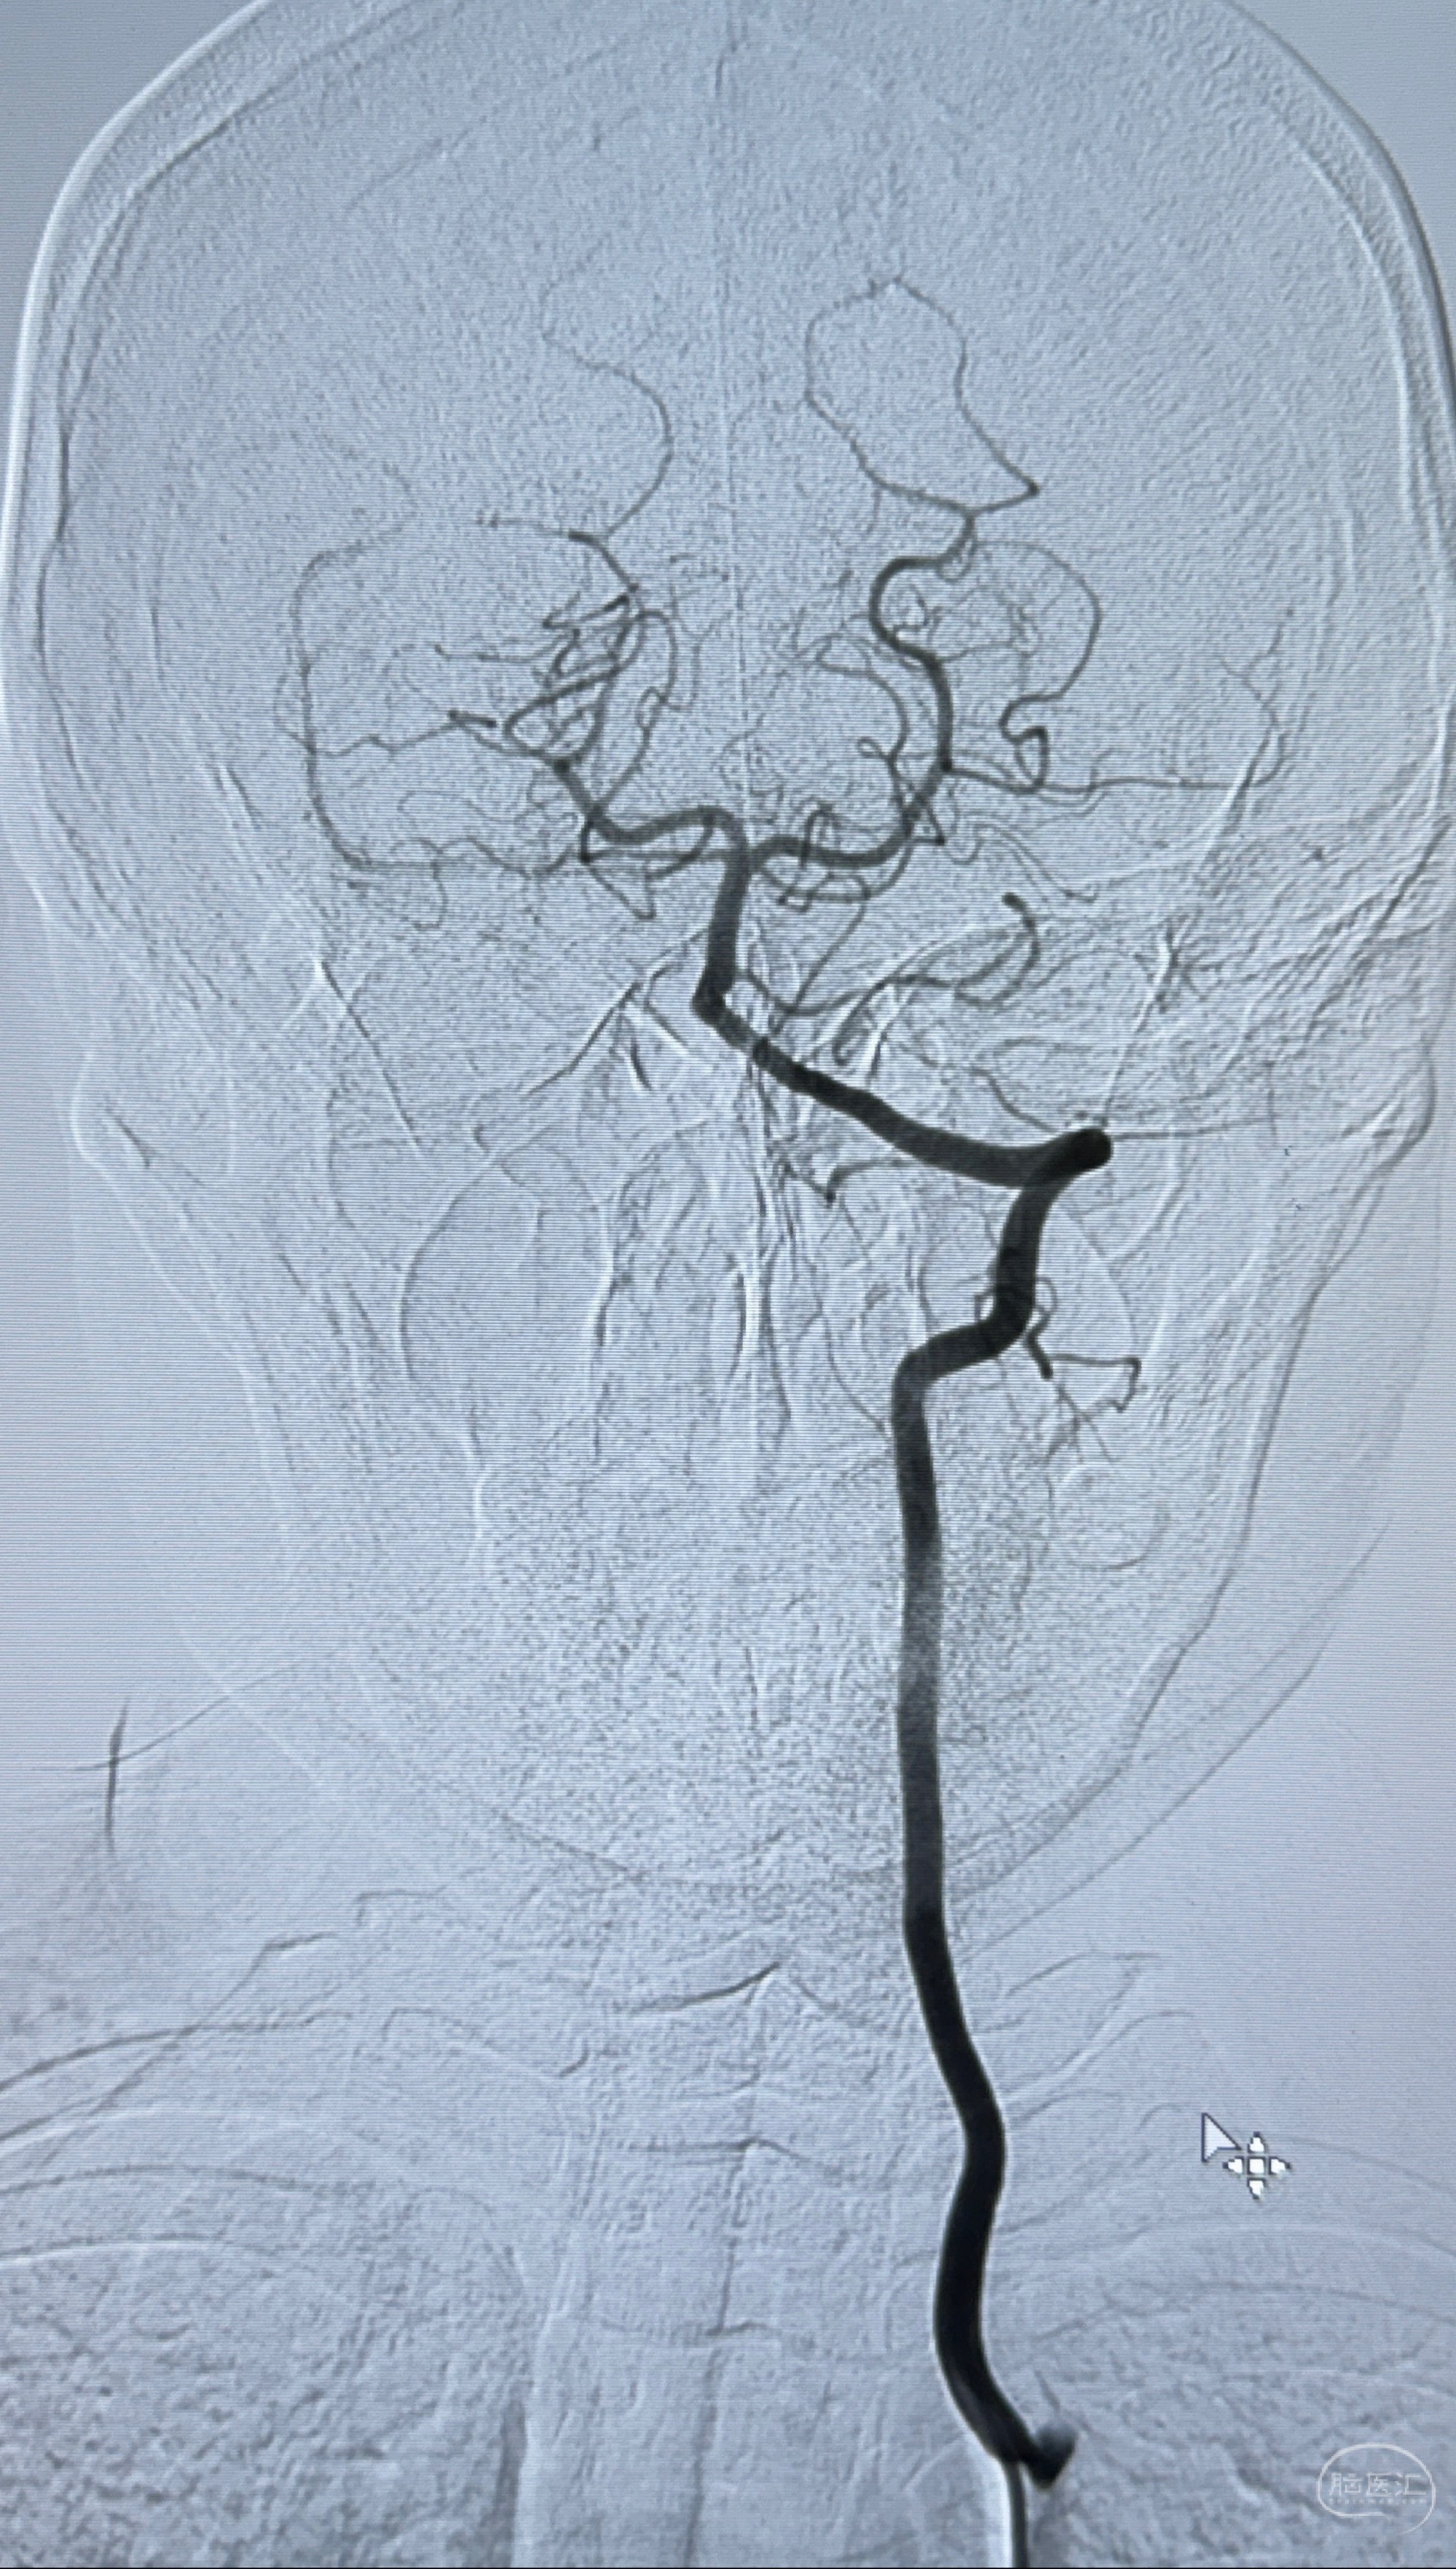

主诉:右侧偏头痛3月,发现左侧颈内动脉眼段动脉瘤5天

现病史:患者诉近4年来时有头痛发作,服用都梁软胶囊、氟桂利嗪对症治疗一月后症状改善,后头痛较少发作。近3月来患者头痛发作频率明显增加,约一月一次,为右侧偏头痛,胀痛,伴恶心呕吐,呕吐后症状可略减轻;遂于2023-11-01至蓝十字脑科医院就诊,查头颅MRI+DWI+MRA提示:左侧枕叶皮层下小斑片缺血或变性灶,右侧大脑前动脉A1段毛糙,显影淡、纤细,建议完善CTA;并于2023-11-03查头颅CTA提示:左侧颈内动脉C6段微小动脉瘤可能(约2mm),右侧大脑前动脉A1段纤细(对侧优势),左侧大脑中动脉提前分叉。现患者无明显不适,为求进一步诊疗颅内血管病变至我科就诊,收治入院。

2023-11-03 蓝十字脑科医院 头颅CTA:左侧颈内动脉C6段微小动脉瘤可能(约2mm),右侧大脑前动脉A1段纤细(对侧优势),左侧大脑中动脉提前分叉。

1.左侧颈内动脉瘤